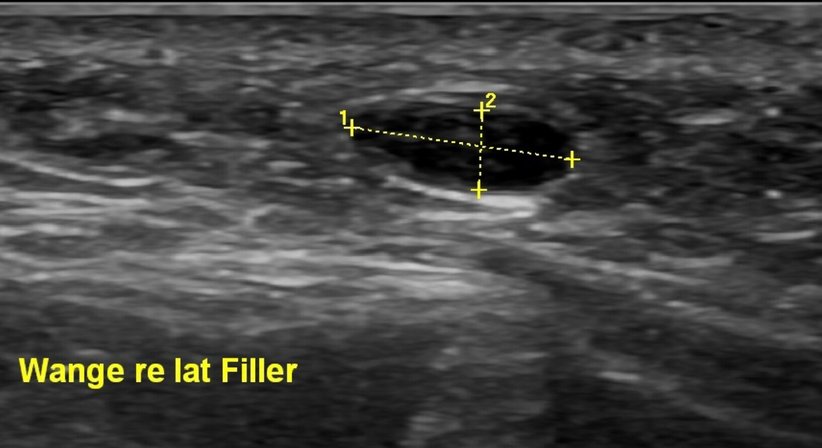

Da Hyaluronsäure-Filler-Depots mit dem hochauflösenden Ultraschall gut sichtbar sind, kann ich diese punktgenau anzielen. Mit einer sehr feinen Nadel injiziere ich Hylase unter Ultraschallkontrolle direkt in das Hyaluronsäuredepot. Innerhalb weniger Stunden beginnt sich die Hyaluronsäure aufzulösen. Je nach Bereich kann der Einstich etwas schmerzhaft sein bzw. kann es zu kurzfristigen Schwellungen kommen. Erfahrung ist bei dieser Behandlung besonders wichtig, da Hylase alle Arten von Hyaluronsäure, einschließlich der körpereigenen, auflöst. Daher müssen Dosierung und genaue Anwendung sorgfältig festgelegt werden.